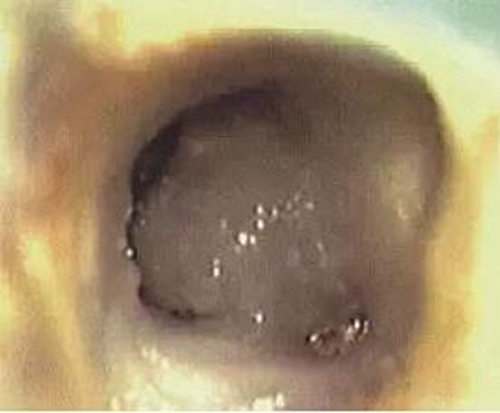

常規(guī)開髓后可在顯微鏡下看到髓室底有C形根管形態(tài),或呈C形(圖1),或呈分號形(圖2)。參考上期所涉及的C形根管分類圖進(jìn)行診斷。

圖1 髓室底根管口呈C形